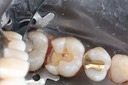

Wayne Chin #15 pre-op

Wayne Chin #15 prep